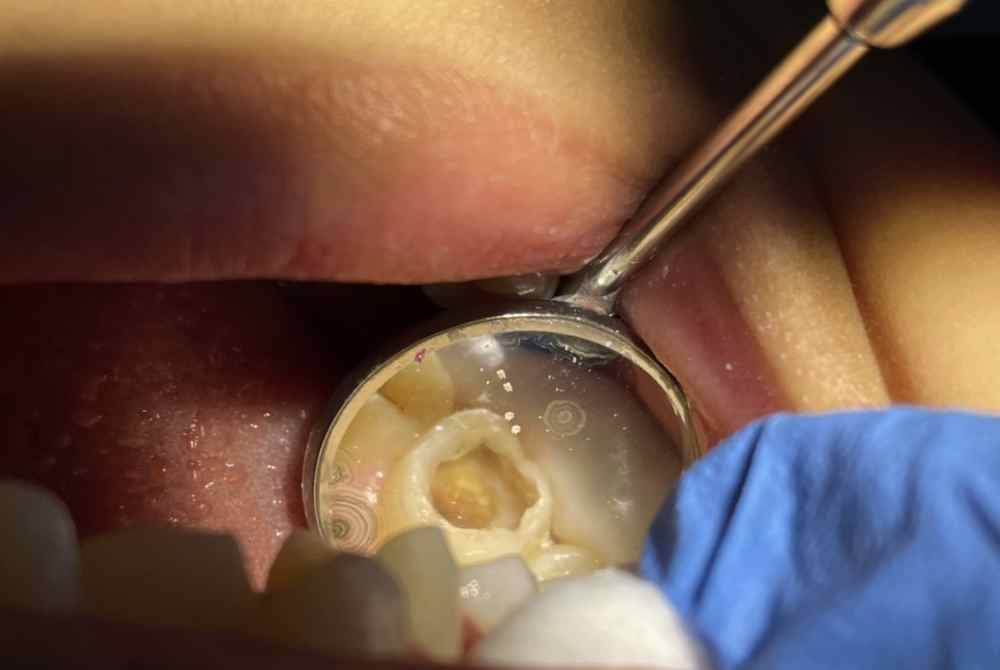

Ini kerana, keadaan struktur gigi anak ini sangat tidak sihat apabila kebanyakan gigi susunya sudah menjadi tunggul gigi selain lebih daripada 10 gigi berlubang dan tidak boleh diselamatkan atau ditampal.

Oleh kerana tiada pilihan, doktor gigi terpaksa mencabut kesemua gigi susu kanak-kanak berkenaan bagi mengelak risiko lebih parah sehingga menyebabkan keradangan pada gusi mahupun hujung akar gigi yang mengakibatkan bengkak, bernanah sekali gus terdedah pelbagai penyakit.

"Kanak-kanak lelaki ini berhadapan masalah karies awal kanak-kanak yang memerlukan kesemua giginya dicabut berbanding usia sepatutnya.